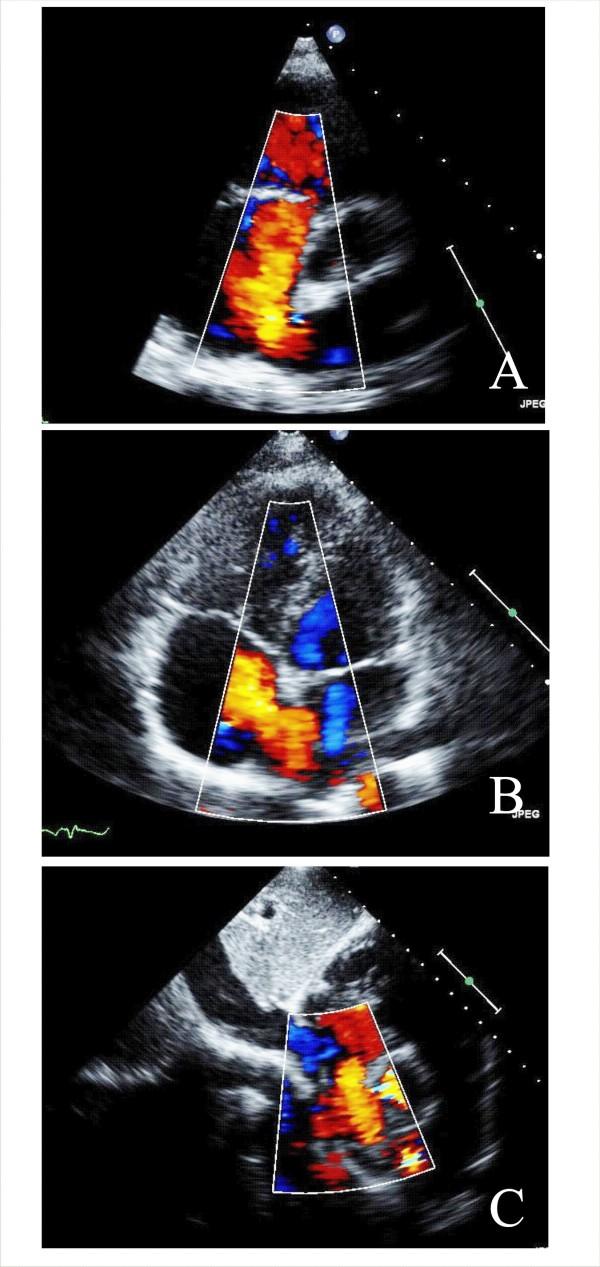

Aortic stenosis and mitral regurgitation, patent foramen ovale, interatrial septal defect, atrial fibrillation and perivalvular leak, are now amenable to percutaneous treatment. These percutaneous procedures require the use of Transthoracic (TTE), Transesophageal (TEE) and/or Intracardiac echocardiography (ICE). This paper provides an overview of the different percutaneous interventions, trying to provide a systematic and comprehensive approach for selection, guidance and follow-up of patients undergoing these procedures, illustrating the key role of 2D echocardiography.

主动脉瓣狭窄、二尖瓣反流、卵圆孔未闭、房间隔缺损、心房颤动及瓣周漏,目前均适合经皮治疗。这些经皮手术需要使用经胸超声心动图(TTE)、经食管超声心动图(TEE)和/或心内超声心动图(ICE)。本文概述了不同的经皮介入治疗,试图为接受这些手术的患者提供一种系统、全面的选择、指导及随访方法,并阐述二维超声心动图的关键作用。